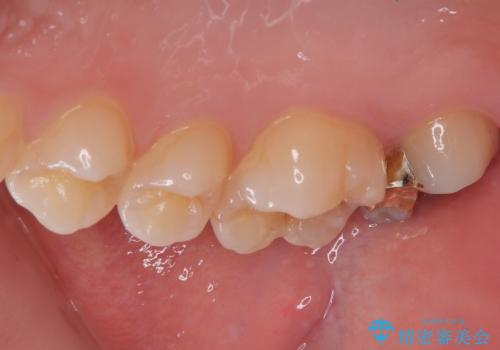

- 他院で虫歯があると言われたので診てほしいとのことで来院された患者様です。来院時特に症状もなく、レントゲンにて右上7に虫歯を認めました。

ゴールドインレーとセラミックインレーで迷われていたので両方のメリット、デメリットを説明してゴールドインレーで治療を進めていくこととなりました。

拡大鏡視野下で虫歯を除去し、ゴールドインレーに適した形に整えました。

歯と歯茎の間に圧排糸と言われる糸を入れてシリコーン印象材にて型どりをしました。